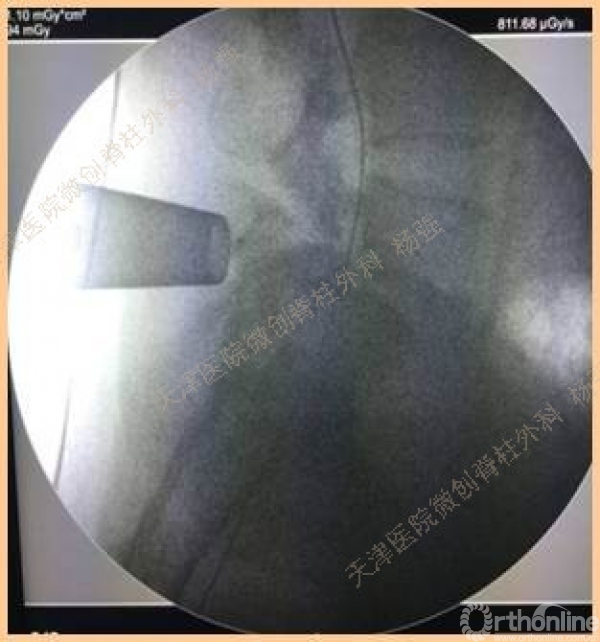

腰5椎体前滑脱I-II°,峡部裂,动力位显示腰5-骶1节段明显失稳

CT、MRI示:腰5椎体前滑脱,腰5/骶1水平间盘突出,腰5双侧椎弓峡部裂